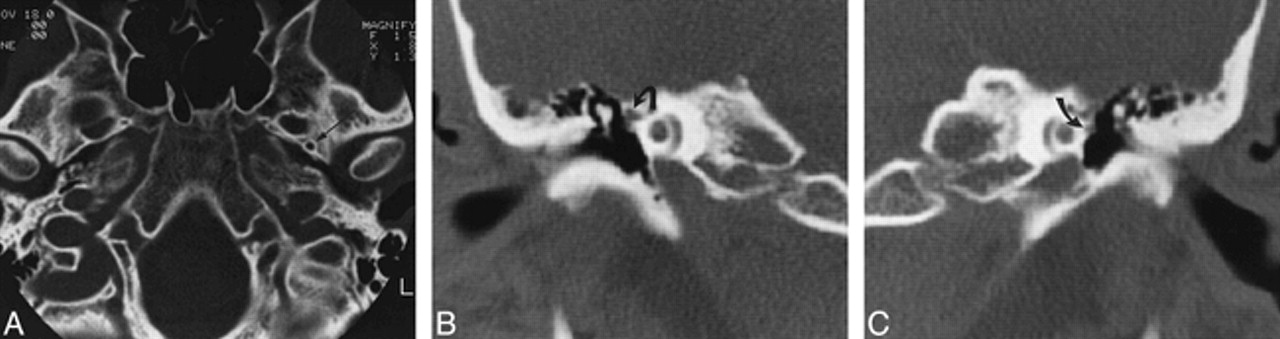

Case 4: 25-year-old woman with pulsatile tinnitus.

A, Axial CT scan shows a normal left foramen spinosum (arrow) and absence of the right foramen spinosum.

B, Coronal CT scan through right middle ear shows the soft tissue at the tympanic segment of the facial nerve is prominent because of the presence of a stapedial artery (arrow).

C, Coronal CT scan through left middle ear shows the tympanic facial nerve is normal in size (arrow).